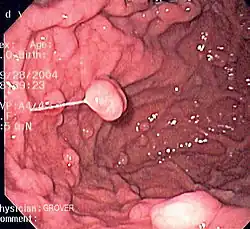

An endoscopy of a normal stomach of a healthy 65-year-old woman

Endoscopic image of a fundic gland polyp

A series of radiographs can be used to examine the stomach for various disorders. This will often include the use of a barium swallow. Another method of examination of the stomach, is the use of an endoscope. A gastric emptying study is considered the gold standard to assess the gastric emptying rate.[50]